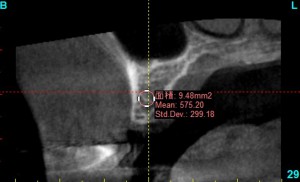

また、患者様のインプラント治療を予定している部分の骨も、同じ患者様であっても、骨の薄い部分、弱い部分、柔らかい部分などがあり、インプラントが最も安定しやすい部分を調べてから、手術時の最大の安定と、術後の長期的な安定の両方のバランスが取れた部分に、インプラントの長さや、太さ、角度などを決定し、インプラントの手術を行います。

mean値を確認しながら、骨の状態を調べ、把握します。

最も骨の硬い部分を中心に安定しやすい場所にインプラントのシュミレーションをします。